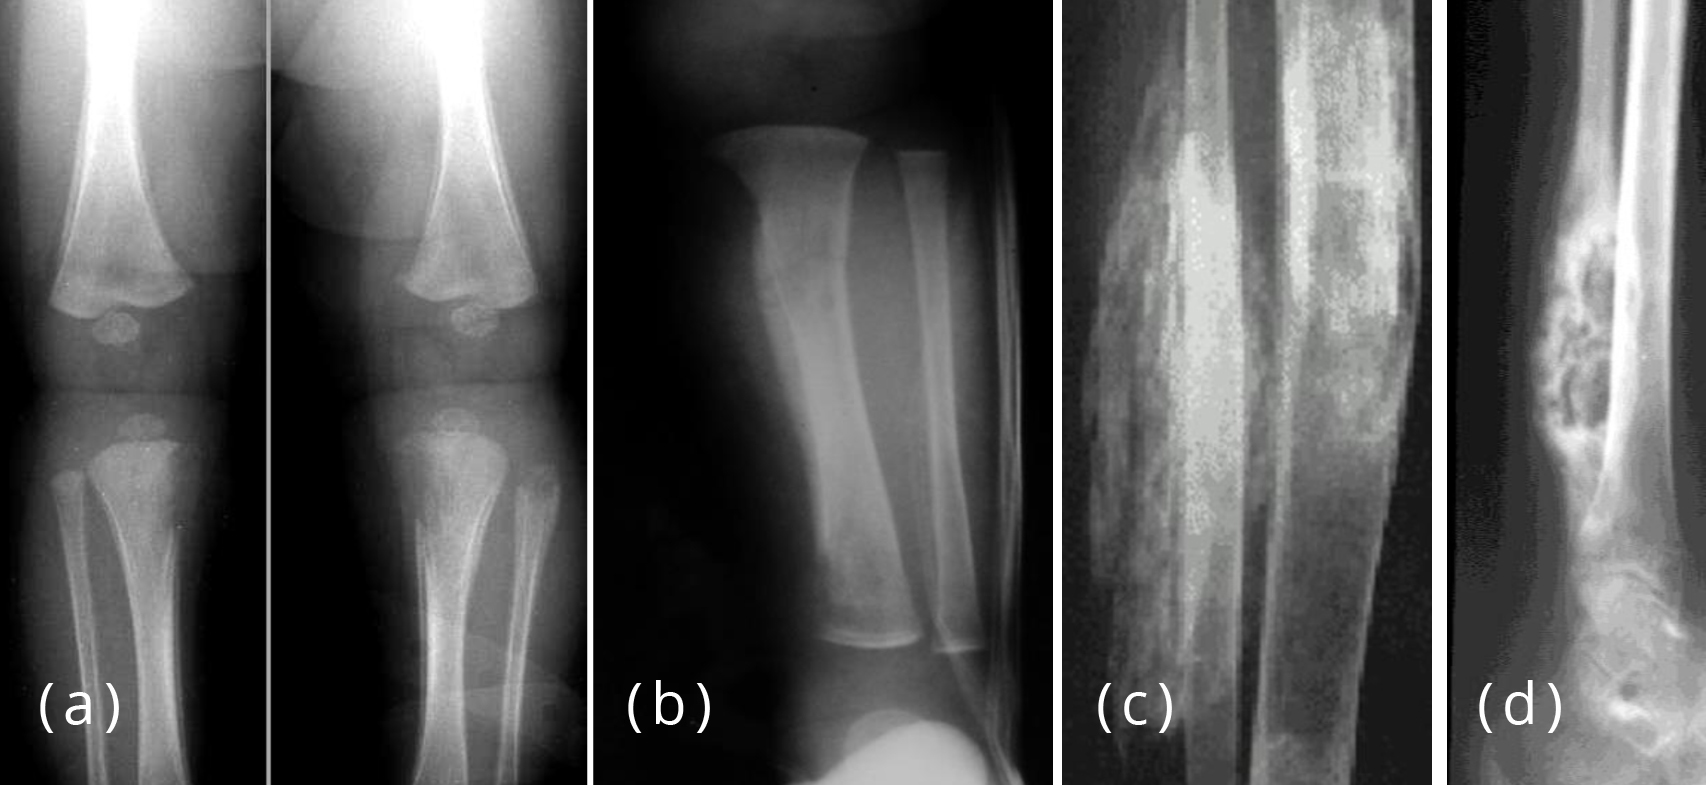

Periosteal reaction & types of periosteal reaction Periosteal Reaction Dental Tumor, infection, trauma, certain drugs, and some arthritic conditions can elevate the periosteum from. Proliferative periostitis is a rare disease, and represents new bone formation. The ultimate goal of any dental treatment is the regeneration of lost tissues. The formation of new bone by periosteum due to an insult is called periosteal bone reaction (pbr). Periosteal reaction results when cortical. Periosteal Reaction Dental.

From www.jfas.org

a, b Linear periosteal reaction osteomyelitis, (a) sickle cell anemia Periosteal Reaction Dental This poster will review the gross and cellular anatomy of the periosteal membrane and a range of periosteal responses. The ultimate goal of any dental treatment is the regeneration of lost tissues. Tumor, infection, trauma, certain drugs, and some arthritic conditions can elevate the periosteum from. Periosteal reaction results when cortical bone reacts to one of many possible insults. Patterns. Periosteal Reaction Dental.

From pocketdentistry.com